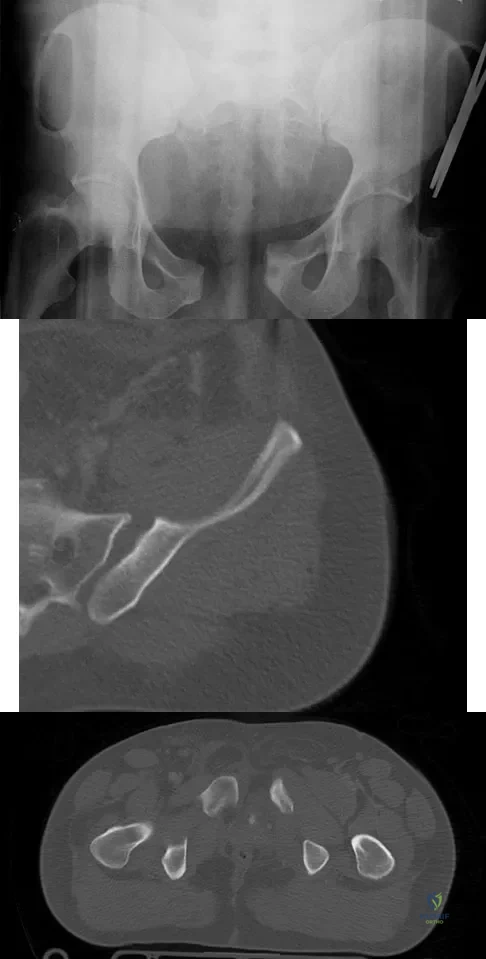

A 22-year-old cheerleader who fell from the top of a pyramid now reports anterior and posterior pelvic pain. A radiograph and CT scans are shown in Figures 43a through 43c. What is the best treatment for this injury?

Explanation

Symphyseal widening of greater than 2.5 cm and less than 5 cm denotes an AP II injury and a rotationally unstable pelvis. An AP II pelvic ring injury is best treated with anterior open reduction and internal fixation. Nonsurgical management is reserved for AP I injuries. Pelvic binders are used only acutely and should not be used for definitive management. Iliosacral screws usually are not necessary in the acute management of AP II injuries. Matta JM: Indications for anterior fixation of pelvic fractures. Clin Orthop Relat Res 1996;329:88-96. Templeman DC, Schmidt AH, Sems AS, et al: Diastasis of the symphysis pubis: Open reduction internal fixation, in Wiss D (ed): Masters Techniques in Orthopaedic Surgery-Fractures, ed 2. Philadelphia, PA, Lippincott Williams and Wilkins, 2006, pp 639-648.